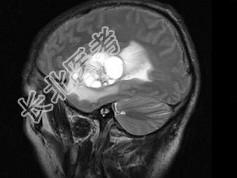

- 单项选择题男,51岁, 1个月前开始头痛,头昏, 根据所提供图像,最可能的诊断是 ( )

A、血管母细胞瘤

B、动脉瘤

C、少枝胶质细胞瘤

D、胶质瘤

E、转移瘤